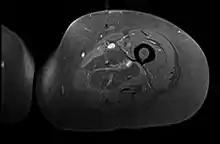

Creatine kinase may be normal or increased probably depending upon the stage of the condition when sampling is undertaken. ESR is elevated. Planar X-ray reveals soft tissue swelling and may potentially show gas within necrotic muscle, Bone scan may show non specific uptake later in the course. CT shows muscle oedema with preserved tissue planes (non-contrast enhancing). MRI is the exam of choice and shows increased signal on T2 weighted images within areas of muscle oedema. Contrast enhancement is helpful but must be weighed against the risk of Nephrogenic Systemic Fibrosis as many diabetics have underlying chronic kidney disease. Arteriography reveals large and medium vessel arteriosclerosis occasionally with dye within the area of tissue infarction. Electromyography shows non specific focal changes.